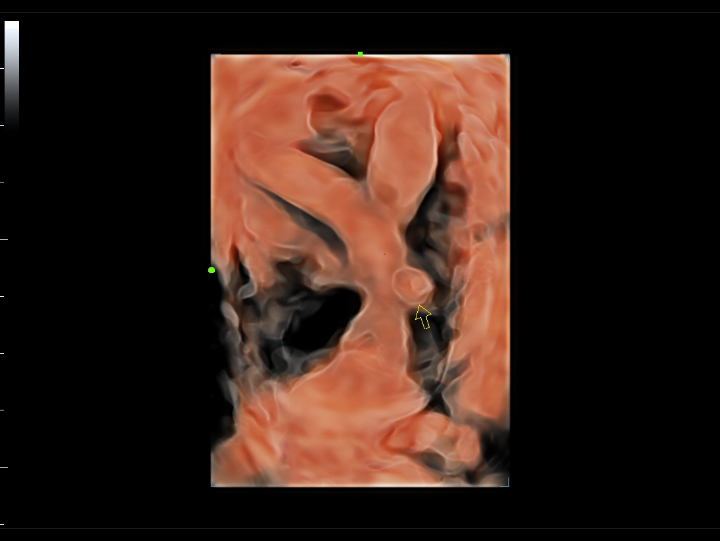

Pelvic ultrasound is considered as the first choice of imaging examination method to evaluate suspected gynecological diseases in women of all ages. Ultrasonography is usually the only necessary imaging examination to diagnose uterine, ovarian and adnexal diseases because of its wide availability, low cost and advantages of no ionizing radiation. With the development of volume ultrasound technology, 3D ultrasound has become a routine gynecological examination item. Through the acquisition of volume data, 3D ultrasound can display the uterus, cervix, ovary and uterine adnexa on any plane, and has more advantages in evaluating the uterine cavity.

UWN+ CEUS provides excellence contrast agent sensitivity and image penetration to get more diagnosis information for gynecology tumor or other difficult diseases. Also MindrayŌĆÖs STE (Sound Trouch Elastogtaphy) can quantitatively evaluate tissue stiffness which is helpful for previse diagnosis of difficult uterus, cervix and ovary diseases.